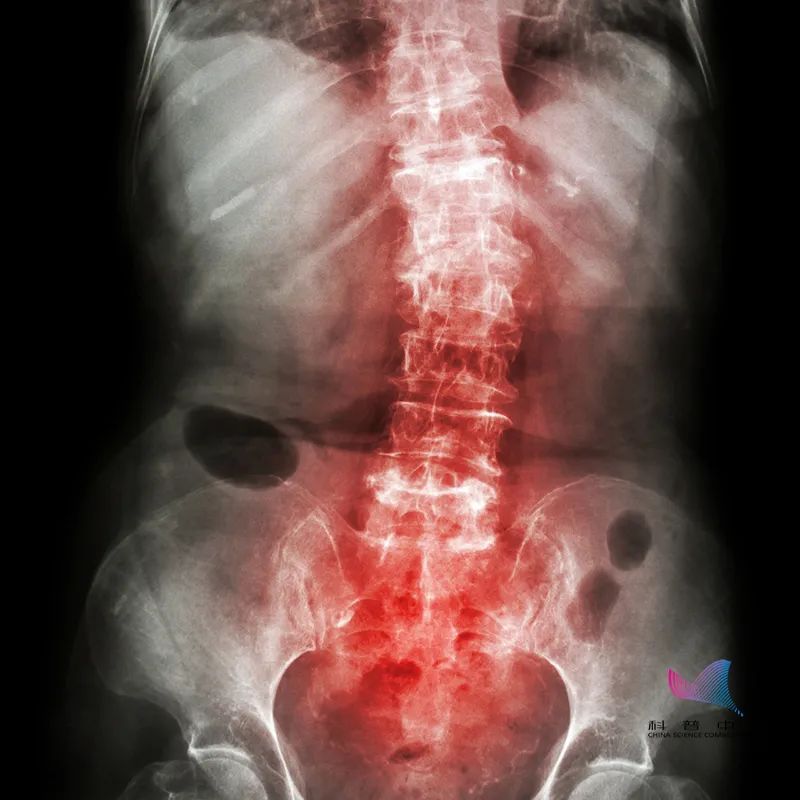

这个“不死的癌症”就是臭名昭著的强直性脊柱炎。

颈椎病或者腰病,则是椎间盘或者椎体出现了病变而引起的,而强直性脊柱炎属慢性炎症性全身性疾病,也就是说和全身的免疫系统密切相关,是一种免疫系统方面的疾病,所以和颈椎病及腰病完全不同。

因此,当出现腰、背、颈、臀、髋部疼痛以及关节肿痛,很有可能是强直性脊柱炎,但是这些症状不足以诊断疾病,需要辅助检查进一步确诊,常用以下几种方法:X线检查、CT检查、骶髂关节MRI、化验检查。

1、脊柱严重强直,严重的脊柱畸形;

2、关节严重畸形,这些晚期症状将使患者的脊柱或(和)髋关节功能丧失而致残,最终严重影响患者的生活质量。